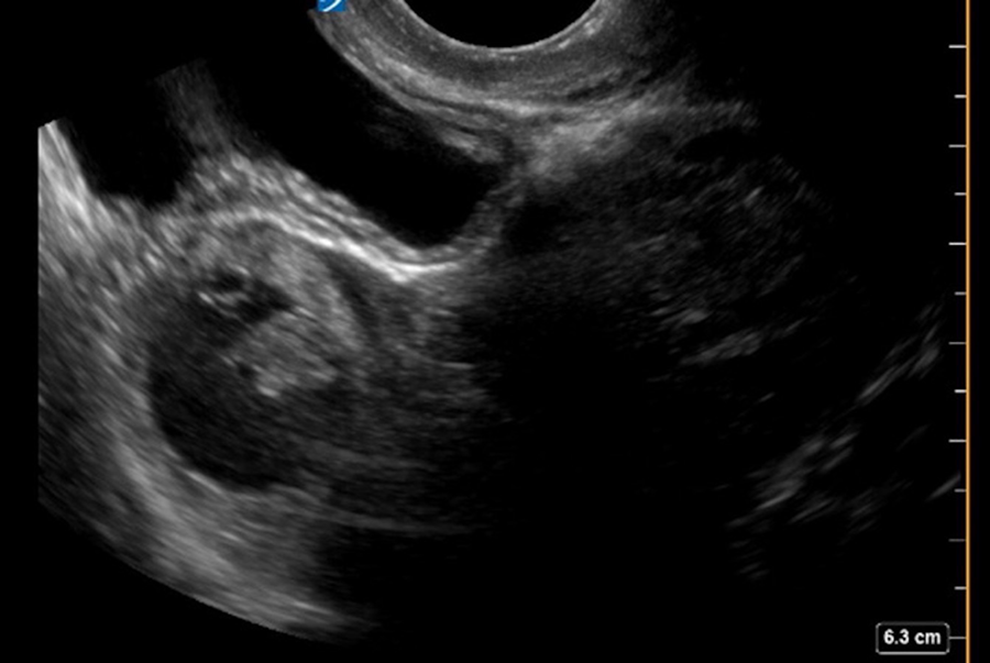

The patient had a positive urine pregnancy test and a serum βhCG resulted at 4979 mIU/mL (negative is <5 mIU/mL). The patient’s transvaginal ultrasound (TVUS) is shown in Figure 1.

Transvaginal ultrasound.

Transvaginal ultrasound of the uterus demonstrates an extrauterine gestational sac and yolk sac with a fetal pole in the left fallopian tube (Figure 2). No fetal cardiac activity was noted.

Transvaginal ultrasound (TVUS) showing ectopic pregnancy, characterized by presence of a yolk sac, gestational sac, and fetal pole in the left adnexa with an empty uterine cavity.